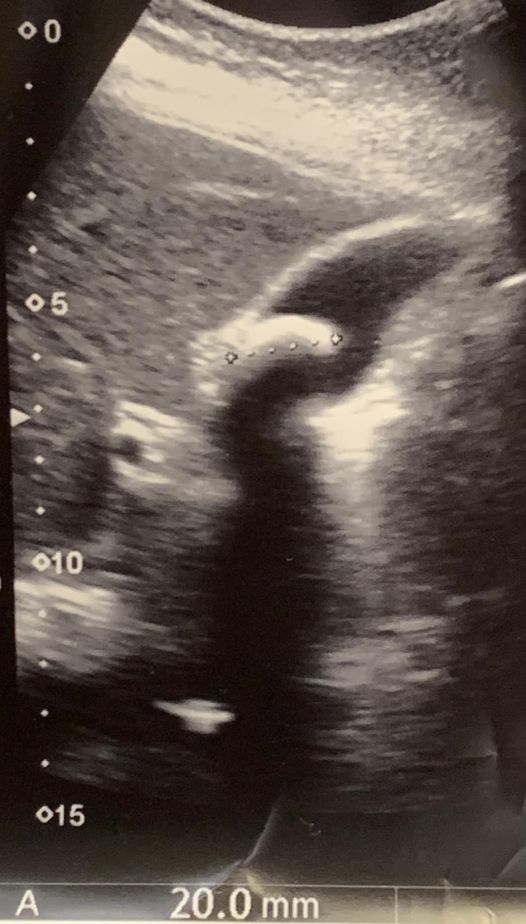

一位40歲的女士為了控制體重3年不吃早餐,但近日因聽說這個方法「會增加2成膽結石風險」而感到非常擔心,便上門求醫,果然超音波竟發現有2公分的膽結石!

肝膽腸胃內科專科醫師蕭敦仁在臉書粉專《蕭敦仁醫師》分享案例時指出,這名女患者用「不吃早餐」這個方法控制體重已有3年,減肥效果不錯,近日因為在中廣「聽醫師的話」節目中聽說「早餐不吃會增加2成膽結石風險」,很擔心膽會有問題,於是特地老遠從台北到桃園看診做腹超,經超音波一看竟有一顆2公分大的膽結石。

蕭敦仁醫師 授權提供 蕭敦仁解釋,空腹時間長,膽汁不排出,本就會增加膽結石風險。建議大家最好確保三餐都要吃,並且飲食中要攝取30%的油脂,而且要是富含不飽和脂肪酸的好油;否則石頭會越養越大顆,到時就非開刀不可了。